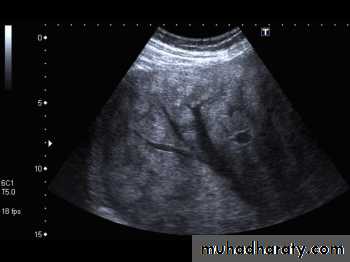

CT scan